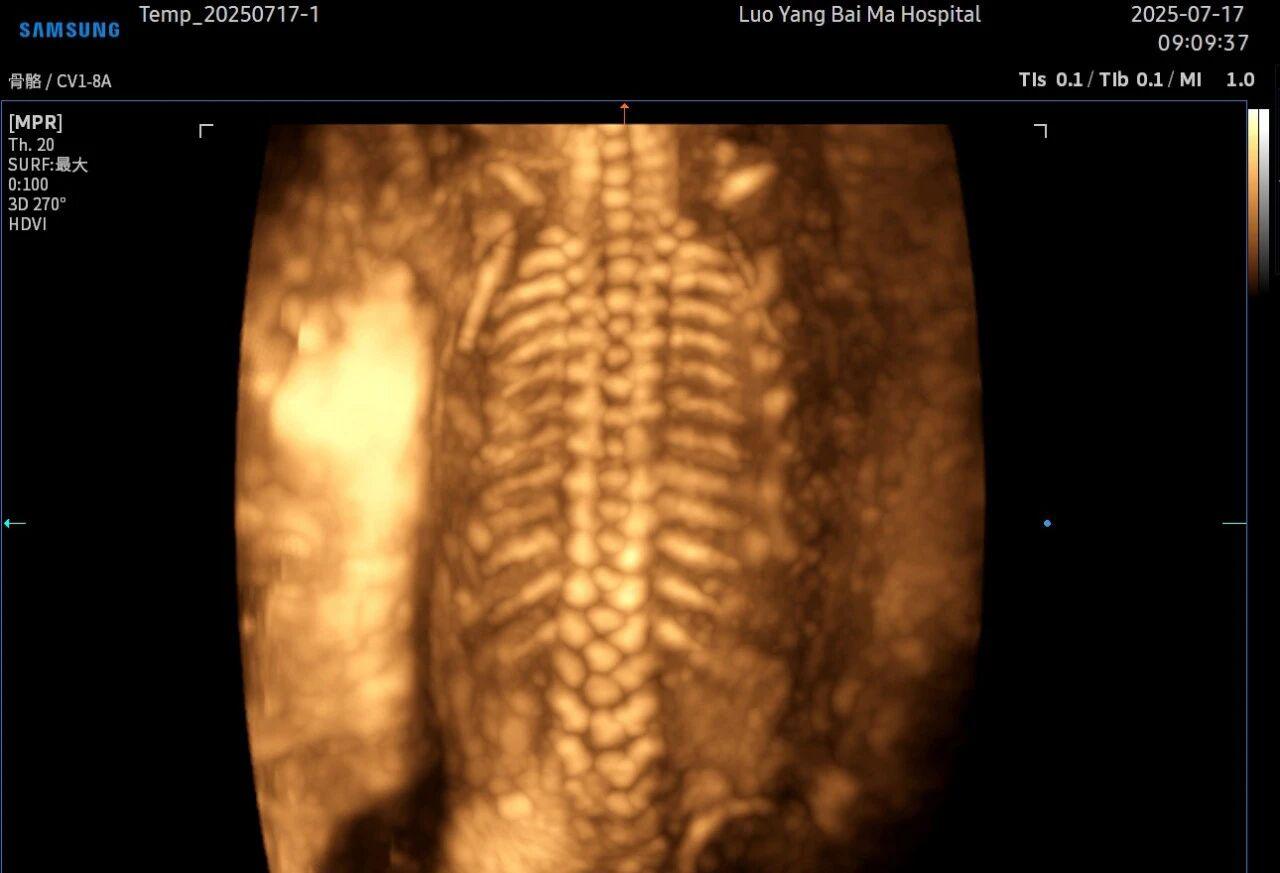

孕中期(通常在22-28周)的大排畸检查是整个孕期至关重要的环节之一。其目的在于系统地筛查胎儿是否存在结构性异常,如唇裂、脊柱裂、大脑、心脏、骨骼发育不良等问题。在这一关键检查中,5D智能彩超凭借其技术特性,展现出了显著的优势。

5D智能彩超拥有更高的分辨率和更强的图像处理能力,能够呈现出接近“IMAX电影画质”的细腻影像 。它采用一种被称为“水晶成像”的技术,能够穿透组织,将胎儿的骨骼、器官和组织结构以极其清晰、立体的形态展示出来。这种高清晰度对于观察胎儿微小的解剖结构细节至关重要,例如手指、脚趾、耳廓形态等,有助于医生发现一些在传统超声下不易察觉的细微异常,为排畸诊断提供了更丰富的视觉信息。

传统超声检查有时会因为胎儿体位、羊水量等因素的限制,导致某些部位观察不清。5D智能彩超技术能够实现对目标结构进行360°全方位、多切面的自由旋转观察。医生可以像“雕塑家”一样,从任意角度审视胎儿的解剖结构,尤其对于形态复杂的心脏、颅脑和脊柱等部位,这种能力可以极大弥补单一平面的局限性,帮助医生更全面地评估其发育状况。